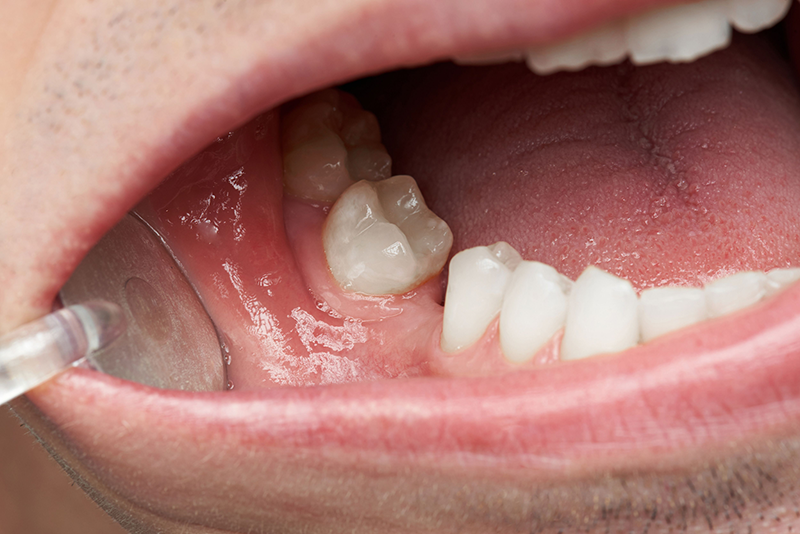

Cô chú/anh chị cần chú ý đến cách chăm sóc răng sau cắm Implant để tránh gây viêm nhiễm

Chăm sóc răng miệng cẩn thận sau khi ghép xương vô cùng cần thiết nhằm đảm bảo vùng phẫu thuật không bị viêm, nhiễm hoặc tổn thương, cụ thể:

• Cách vệ sinh: Vệ sinh bằng bàn chải lông mềm, không tác động trực tiếp vào vùng vừa ghép xương/cắm Implant, không súc miệng bằng nước muối/nước súc miệng có tính sát khuẩn mạnh trong 24 giờ đầu tiên để ngăn ngừa tình trạng cắm Implant bị viêm.